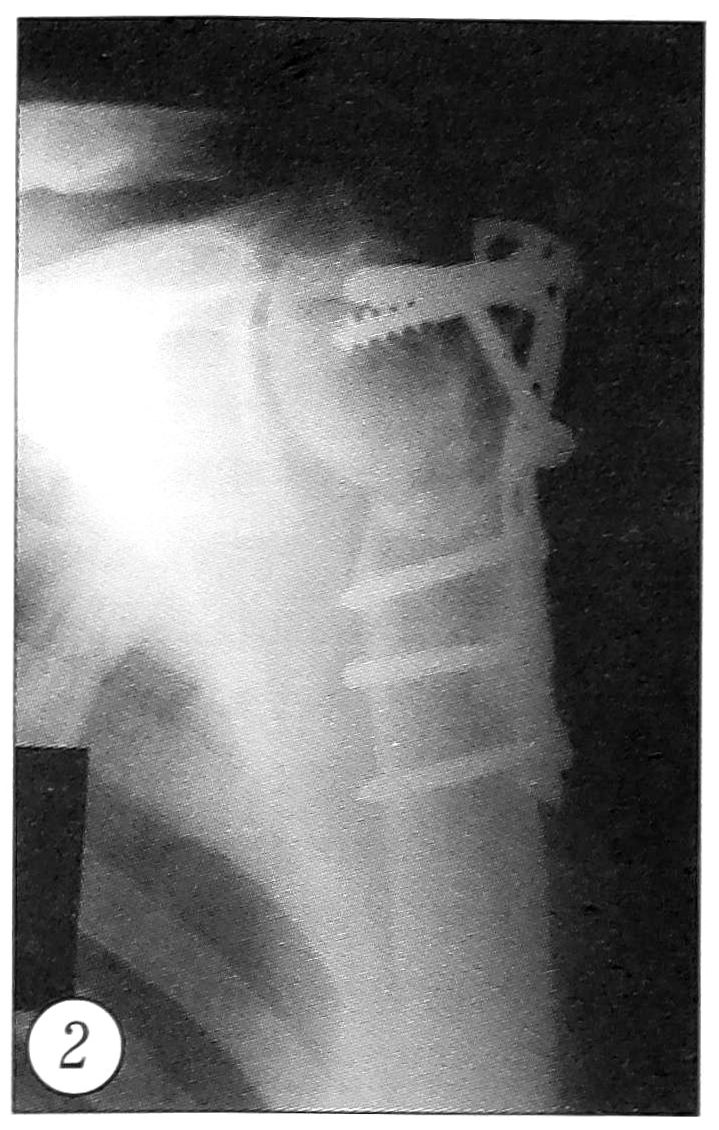

Оценку функциональных результатов проводили по модифицированной системе American Shoulder and Elbow surgeons [5]. Отдаленные результаты изучены у всех больных в сроки от 7 до 48 мес. Средняя продолжительность стационарного лечения составила 20,8 дня (от 11 до 40 дней). Инфекционных осложнений и нестабильности металлоконструкций не отмечено. У 2 пациентов после остеосинтеза трех- и четырехфрагментарных переломов развился асептический некроз головки плечевой кости (рис. 2).

Рис. 2. Асептический некроз головки плечевой кости у больного 64 лет через 4 мес после остеосинтеза по поводу трехфрагментарного перелома.